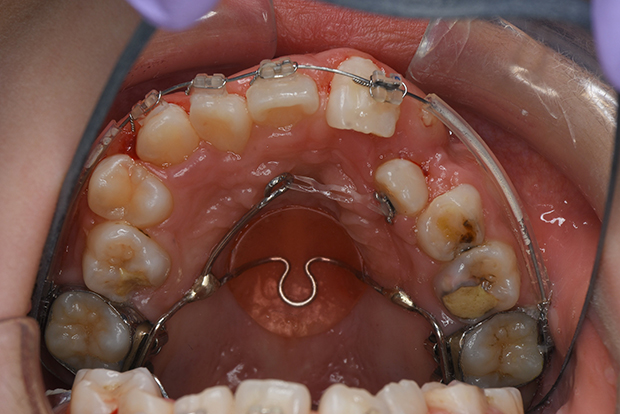

【埋伏歯】下顎前突 小児矯正 表側マルチブラケット装置

| 主訴 |

上の歯が出てこない 受け口 |

||

|---|---|---|---|

| 診断名 |

上顎左側中切歯、側切歯の埋伏歯および側切歯、犬歯の移転歯を伴う反対咬合 |

||

| 年齢 | 8歳 | 性別 | 女子 |

| 治療に用 いた装置 |

舌側弧線装置 唇側マルチブラケット装置 (メタルワイヤー) | 抜歯部位 | 非抜歯 |

| 治療期間 ・回数 |

3年10か月・46回 | 治療費 概算 |

約40万円 (調整料を含む) |

| 治療内容 詳細 |

前歯が生えてこないのをかかりつけの歯科医院にて指摘され、ご紹介された患者様です。虫歯も多い子でしたが、虫歯の治療、管理も同時に行い、小児矯正だけで綺麗に治りました。 |

||

| リスク・ 副作用 |

装置による違和感 疼痛 虫歯のリスクなど |

||